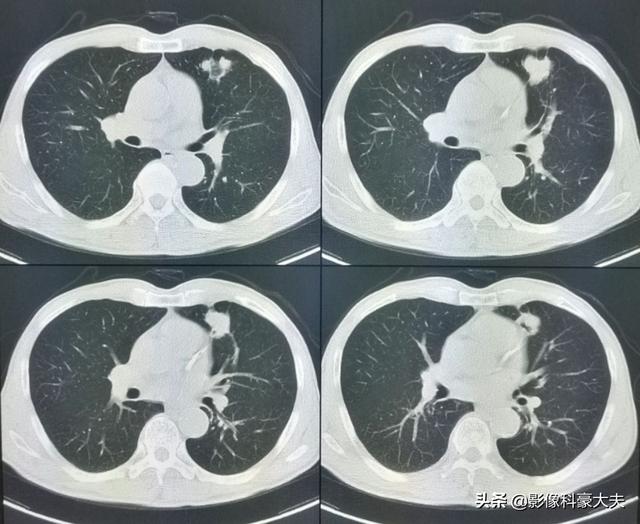

左肺にあるこの不規則な結節が原発巣で、わずか2.6cmしかない。このような骨転移を伴う肺がんは、もはや手術不可能です。肺がんはあまりにもありふれた病気であり、初期症状の中には非典型的なものや無症状のものさえあるからだ。肺がんの約30%では、転移の症状が最初の症状であり、さらなる肺がんが発見される前に転移が最初に発見される。

直近のCT検査の結果、原発巣はかなり縮小しており、5年以上保菌したまま生きられたのは幸運だった!